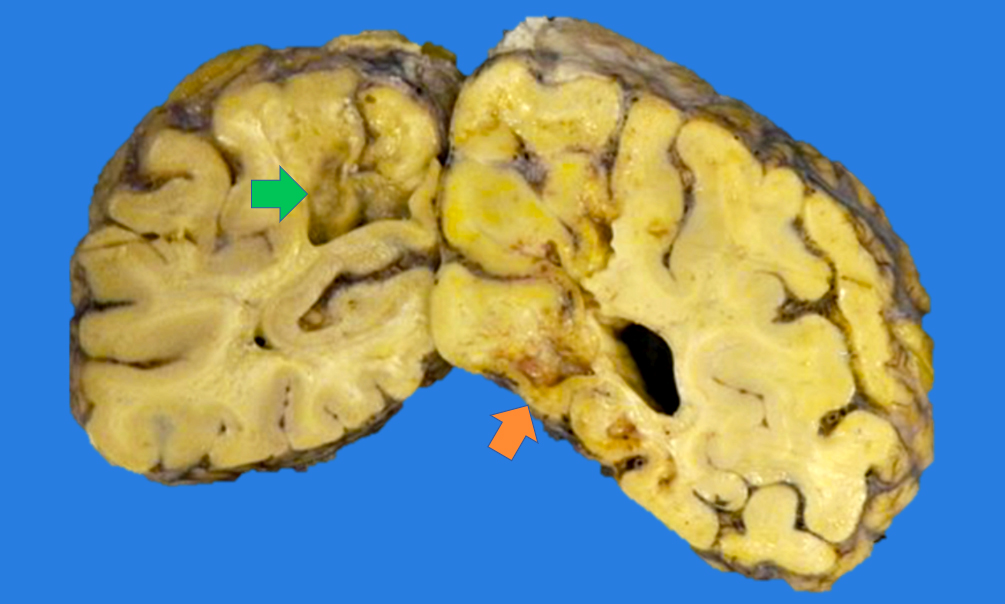

Gross description

- 2 days to a few months (Histopathology 2011;58:333)

- Marked tissue softening

- Cracking artifact: demarcates the necrotic area

- Tissue edema (e.g., midline shift, narrowing of the sulci, convexity flattening)

- Dusky discoloration and blurring of gray-white matter junction

- Chronic (months - years)

- Cavitation (i.e., cystic infarct)

- Thin cortical remnant overlying the cavitation

- In long term survivors of severe global hypoxic ischemic encephalopathy, a markedly thin cortex can be observed due to laminar necrosis

- Lateral ventricle asymmetry can be seen (i.e., ex vacuo ventricular dilation of the affected hemisphere)

Gross images